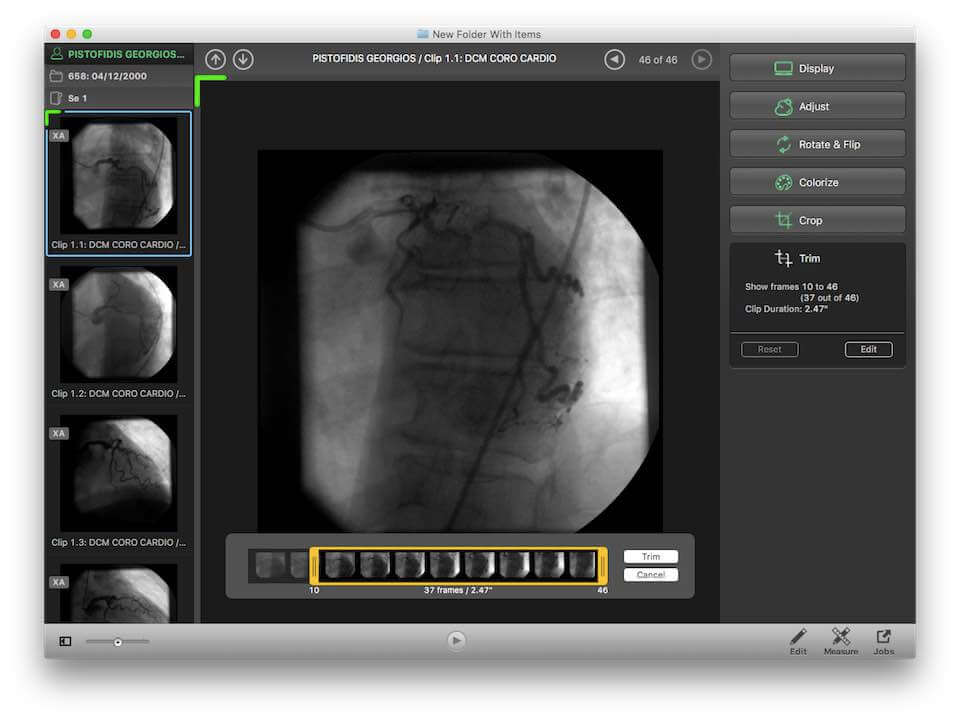

Miele LXIV is a free DICOM viewer for Mac operating systems. It has advanced features including MPR, MIP, volume rendering, and image fusion. In addition, it also allows 4D viewing of cardiac CTs. It is PACS-integrated and can send and receive files from a PACS database.

| 16. | Miele LXIV | Mac OS X | PACS integrated | Y | Y | Y | Y | 50 MB | Intel processor | Free to use |